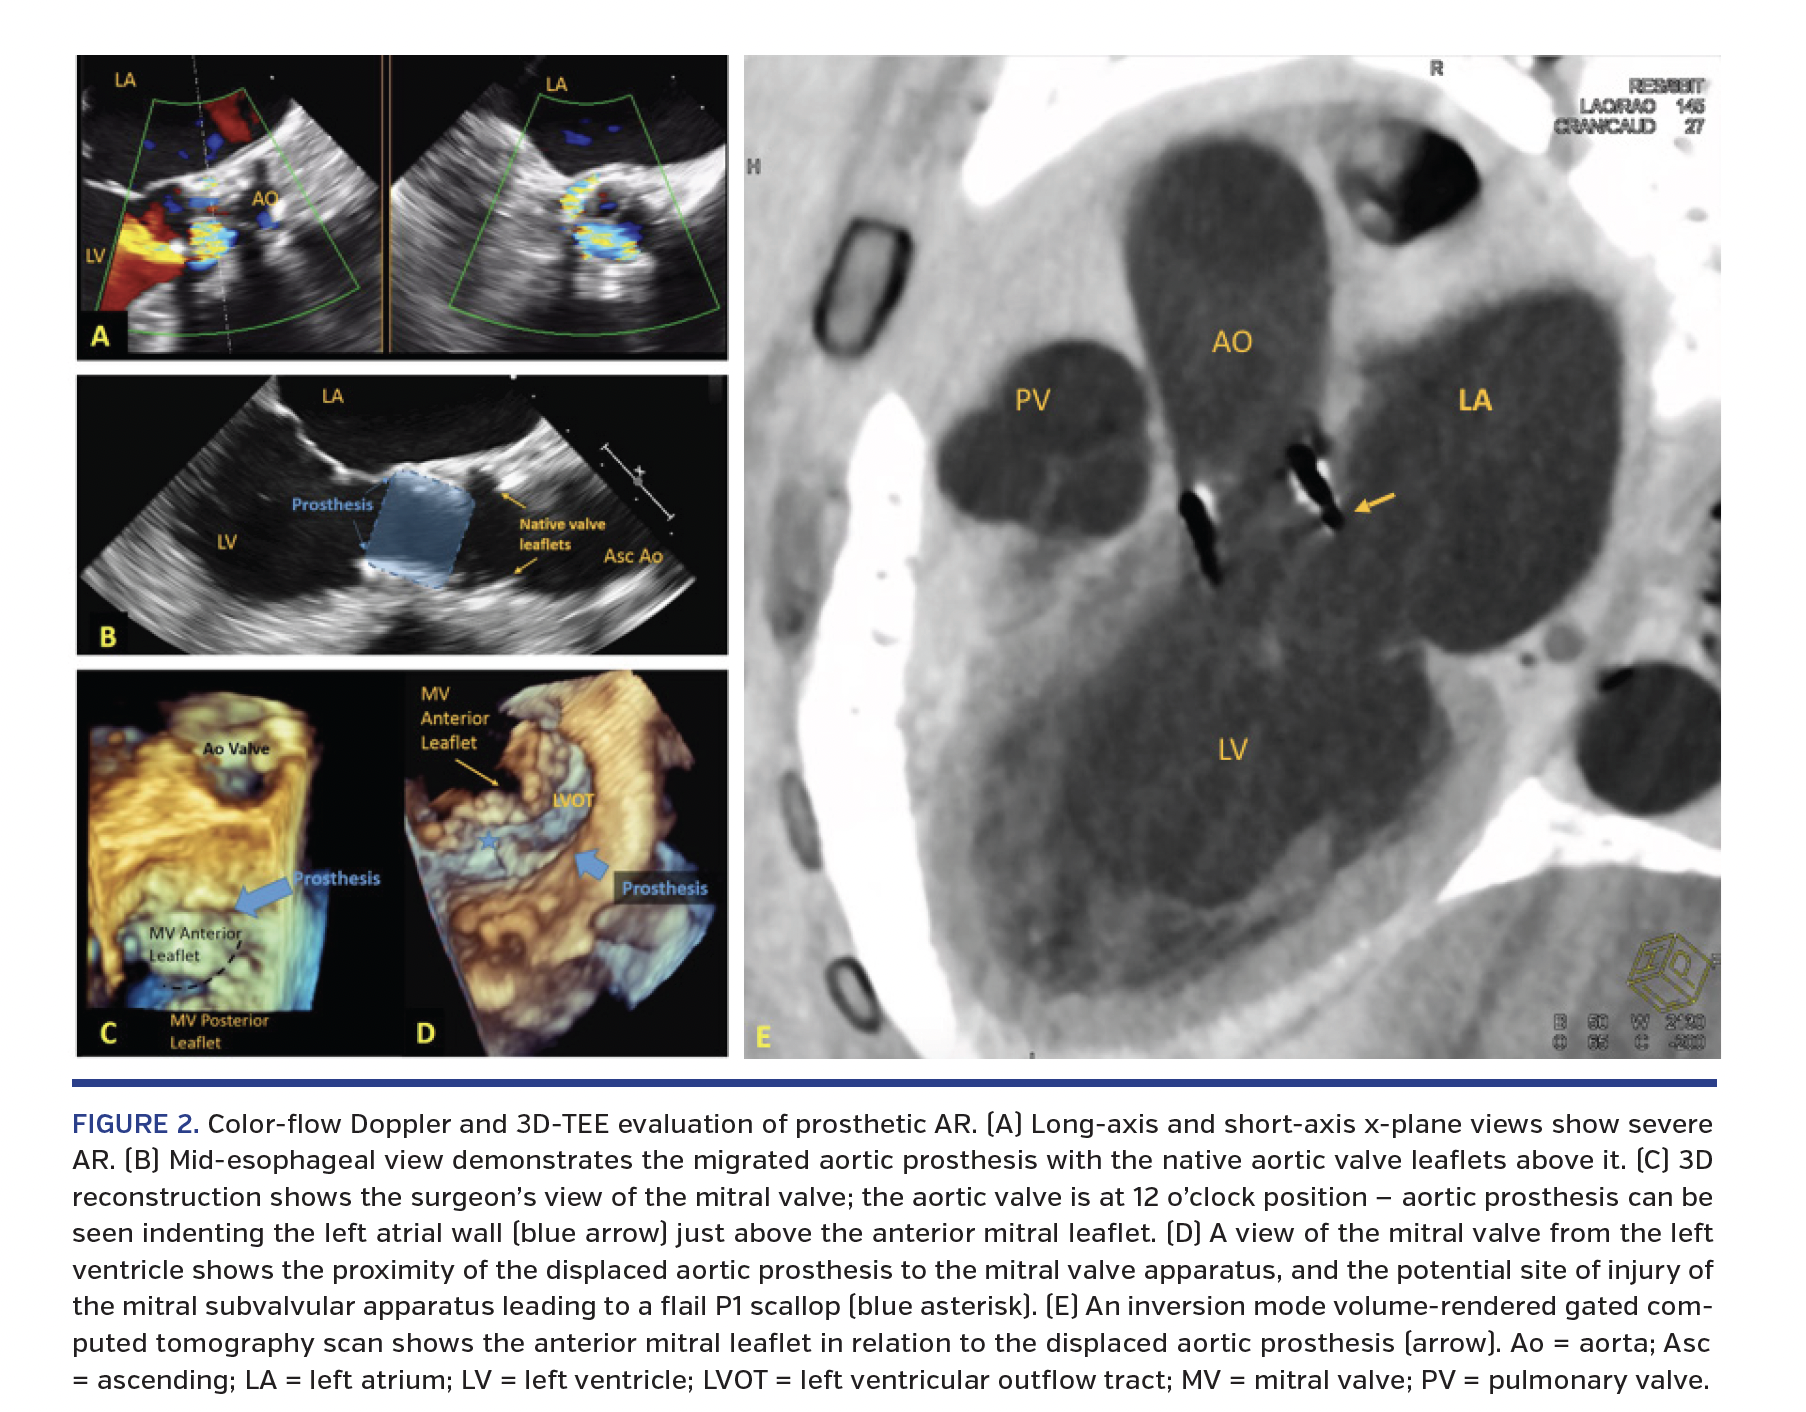

A 70-year-old woman was re-admitted to the emergency department with recalcitrant heart failure symptoms that had initially abated following initiation and optimization of diuretic therapy. Past medical history was significant for heart failure with preserved ejection fraction, chronic obstructive pulmonary disease, and aortic stenosis treated with transcatheter aortic valve replacement (TAVR) 3 years prior, with a 23 mm Edwards Sapien XT valve (Edwards Lifesciences). Physical exam was remarkable for bibasilar crackles, 3/6 pansystolic murmur heard best at the apex with radiation to the axilla, and 3/6 harsh, diastolic decrescendo murmur heard best at the lower left sternal border. Transthoracic echocardiogram showed severe mitral regurgitation (MR) with an eccentric posterolateral jet and moderate aortic regurgitation (AR) with peak velocity of 3.8 m/sec, mean gradient of 32 mm Hg, and valve area of 1.2 cm2. Three-dimensional transesophageal echocardiogram (3D-TEE) demonstrated two MR jets (Figure 1) and severe AR. There was a migrated aortic prosthesis below the native aortic valve leaflets (Figure 2). In addition, the displaced prosthesis may have disrupted the mitral subvalvular apparatus, leading to a flail P1 scallop. These findings were confirmed by inversion mode volume-rendered and multiplanar gated computed tomographic (CT) reconstruction (Figure 2E; Videos 1 and 2). A valve-in-valve TAVR was planned. Intraprocedural cone-beam CT imaging and aortic root angiogram showed the “slipped” Sapien XT valve (in comparison with the aortic root angiogram from 3 years ago) with severe AR, respectively (Figure 3). There was complete resolution of severe AR following valve-in-valve TAVR with a 23 mm Edwards Sapien 3 valve (Figure 4; Videos 3-5).